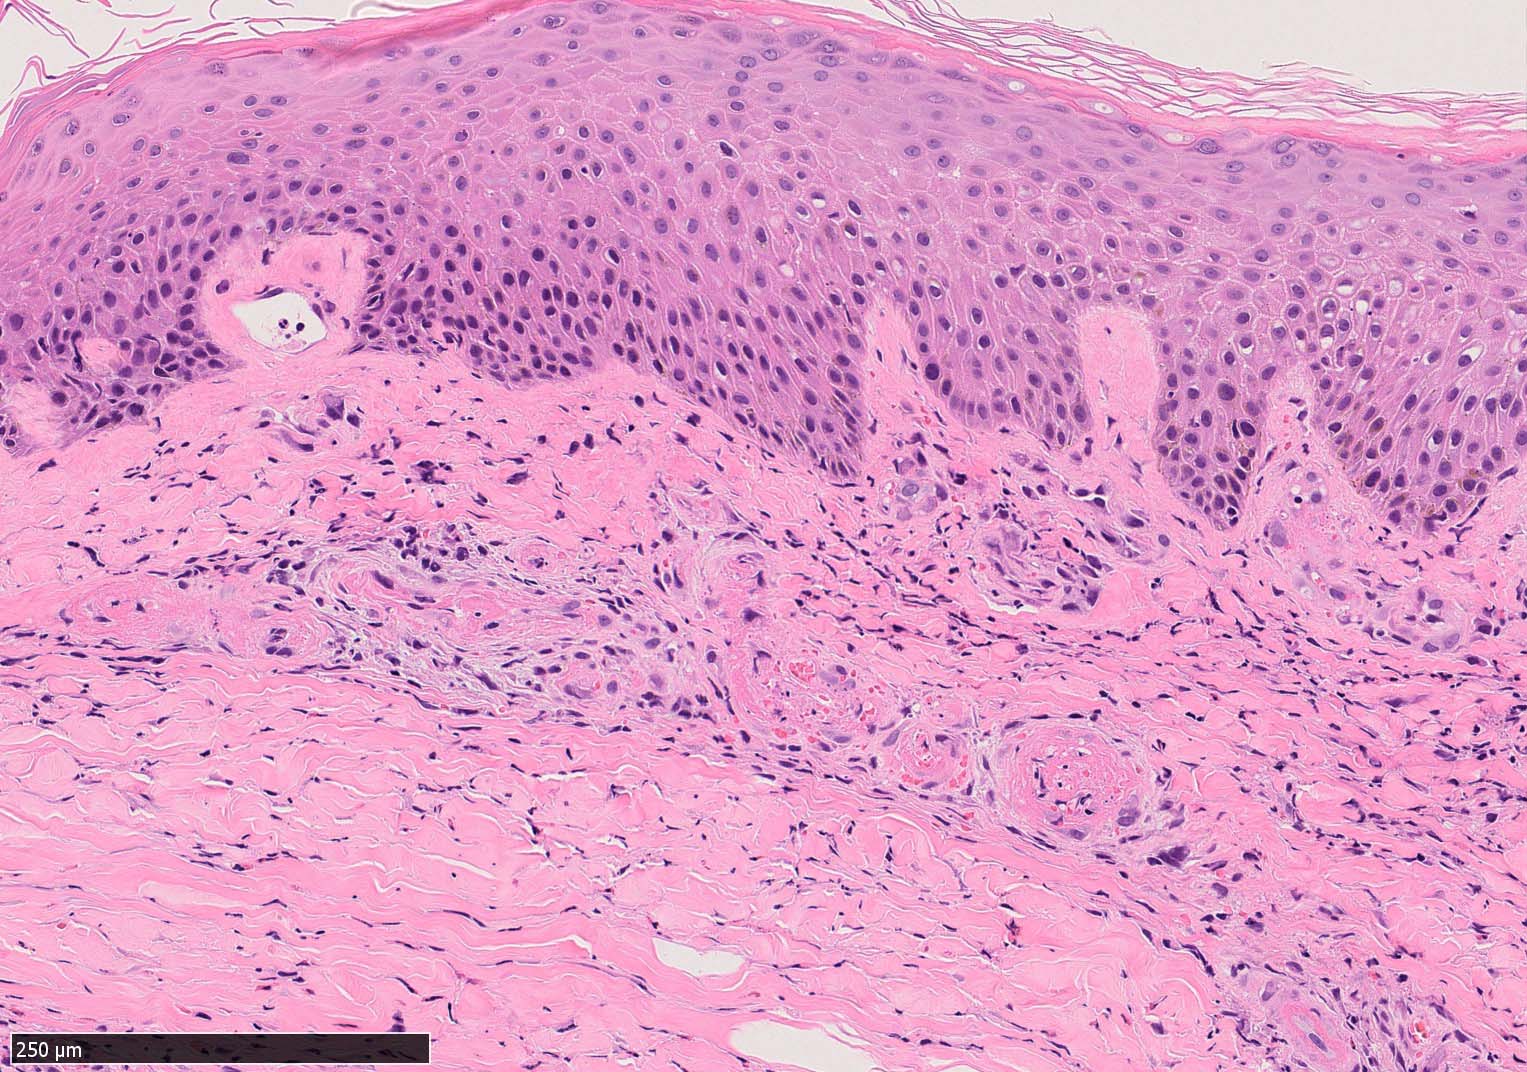

IWT-case03 マダニに咬まれた. 自分で虫体を除去したが傷がびらん化し, 発熱を来したため, 来院する.

痂皮の下に硝子様凝固物があり, 周囲には壊死組織が形成されている. 近傍の細血管には凝固物による閉塞の所見があるように見える. 連続する細血管には, fibrinoid necrosisを呈する壊死性血管炎が認められる.